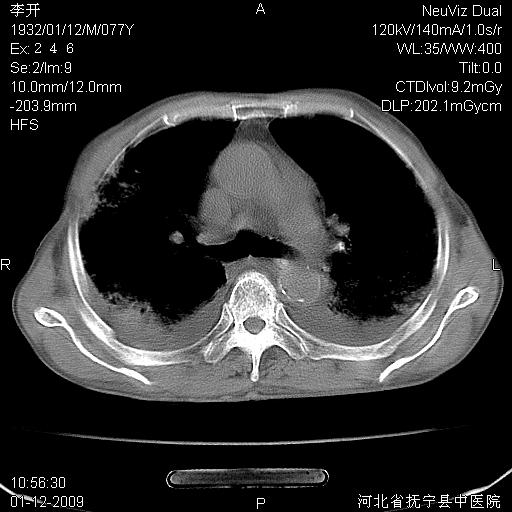

以下是引用黑白光影在2009-1-19 16:49:00的发言:[br]心衰肺水肿;心包、胸腔积液;冠脉钙化;肺部感染。